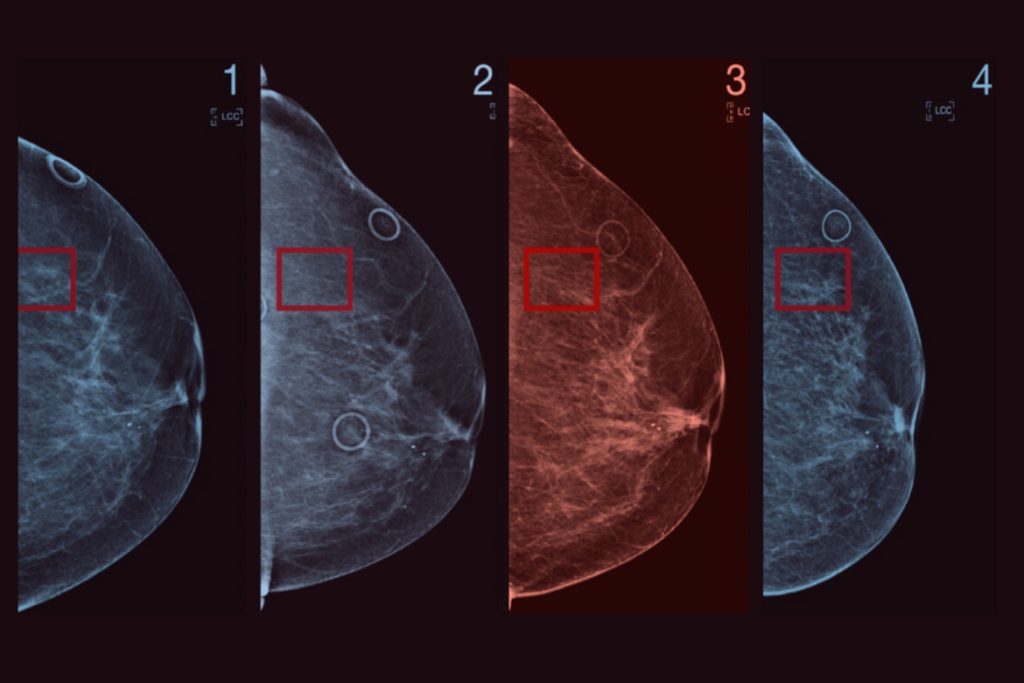

Read moreLatest Advances in Early Breast Cancer Detection